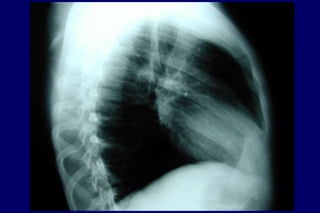

Radiografia

de tórax

Excluir outras

doenças

Bolhas

Hiperinsuflação

DIAGNÓSTICO História Exame físico Normal / quase Hiperinsuflação Murmúrio vesicular diminuído Sinaisde cor pulmonale mMRC-CAT Radiografia de tórax Excluir outras doenças Bolhas Hiperinsuflação Tabagismo Tosse Dispnéia Sibilos Exposição